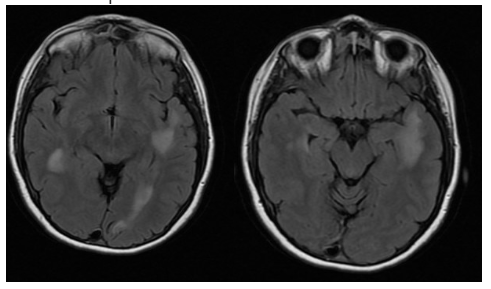

In January of last year, I had just finished up my steroid treatment from a relapse I had in December. At the time, I was unaware of how bad my relapse actually was. The doctors at the hospital I was at told me I had “a few active lesions” and didn’t go into too much detail. I didn’t really have many symptoms at all, so I figured it was mild. When the MRI results were shared with my MS Specialist in Houston, he met with me and informed me that I had several large lesions the size of tumors. He told me “this is really, really bad”. It was very hard hearing my doctor say this to me and it took me by surprise. He told me I had what is called “tumefactive-MS”, which I had never heard of. Essentially, my lesions were the size of tumors (pic below).

On July 17th, I went in for my 3 hour MRI (you read that right). These MRIs are brutal. I dread them every single time. This was the first time I was offered music and a break halfway thru, which helped a ton! After the MRI came the waiting game. I’ll spare you the details, but after a mix up with the radiologist, followed by him going on a two week vacation, I FINALLY received my results on August 4th. Not only were things stable, but significantly improved!! Below is a pic showing how much smaller my lesions were after only 6 months!